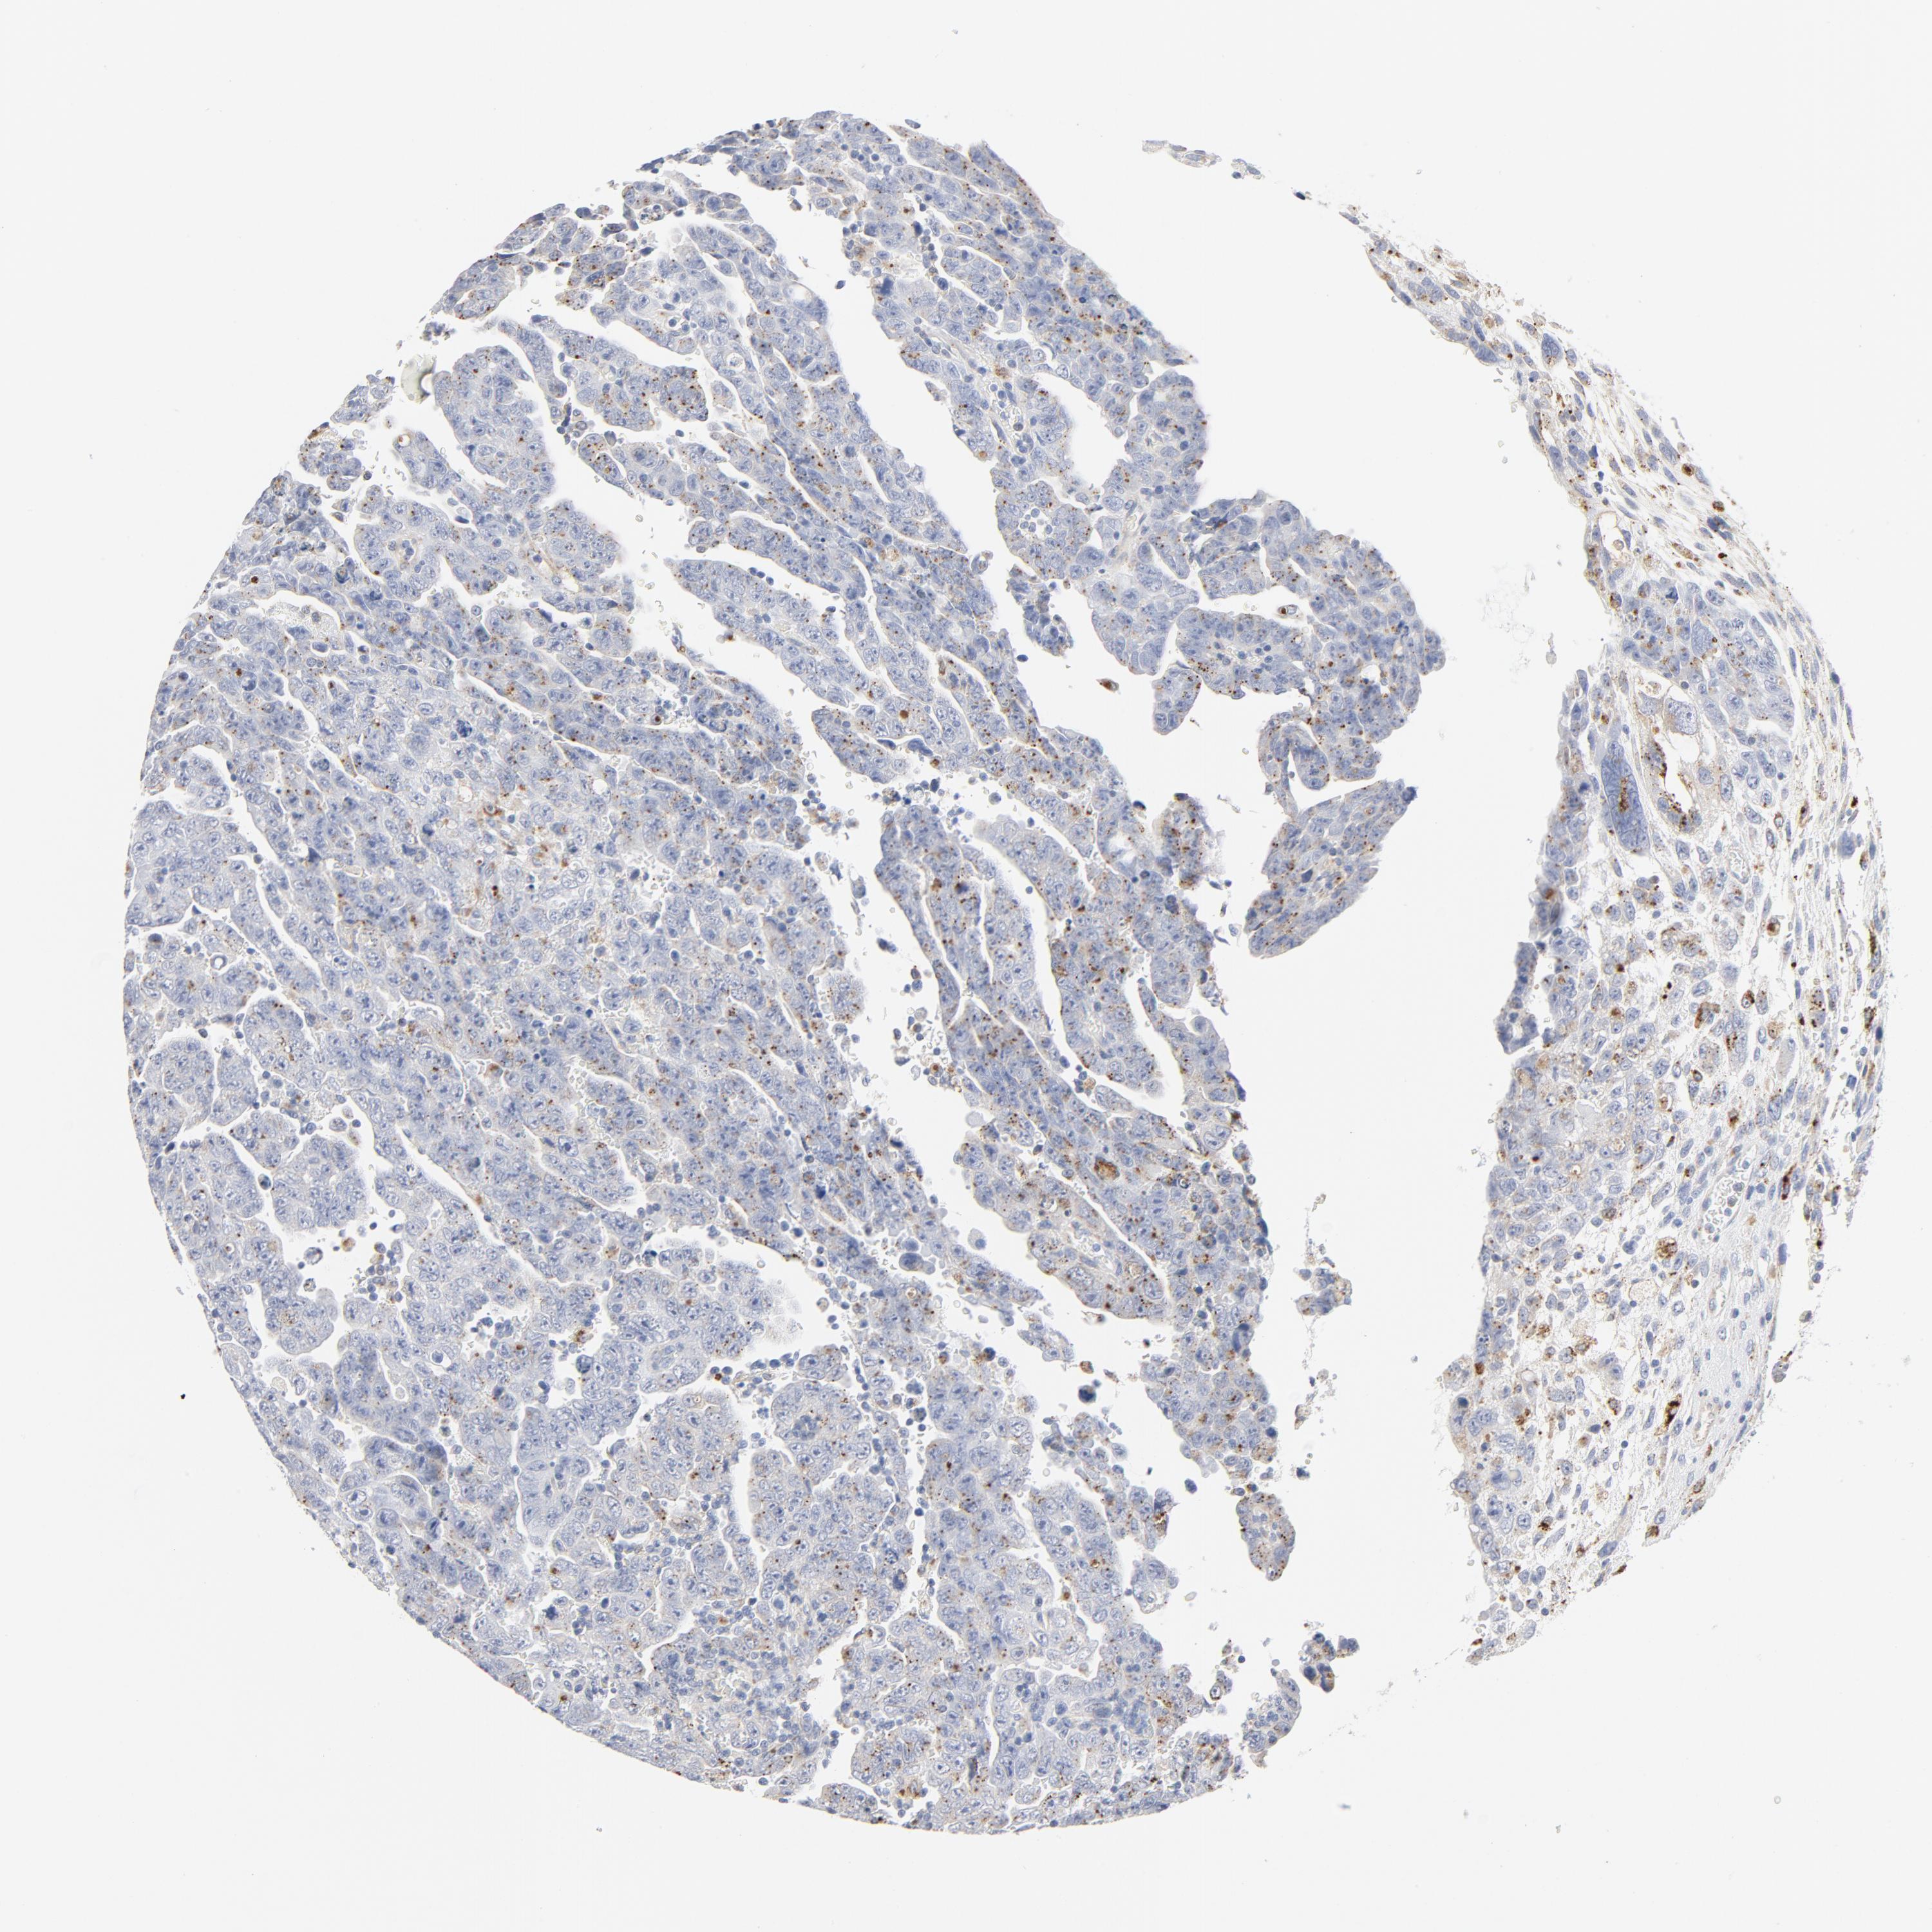

TESTIS CANCER - Protein expressioni

A mouse-over function shows sample information and annotation data. Click on an image to view it in a full screen mode. Samples can be filtered based on level of antibody staining by selecting one or several of the following categories: high, medium, low and not detected. The assay and annotation is described here.

Note that samples used for immunohistochemistry by the Human Protein Atlas do not correspond to samples in the TCGA dataset.

Antibody stainingi

Antibody staining in the annotated cell types in the current human tissue is reported as not detected, low, medium, or high, based on conventional immunohistochemistry profiling in selected tissues. This score is based on the combination of the staining intensity and fraction of stained cells.

Each image is clickable and will lead to virtual microscopy that enables deeper exploration of all samples and also displays staining intensity scores, fraction scores and subcellular localization as well as patient and tissue information for each sample.

Antibody HPA003756

Staining

High

Medium

Low

Not detected

Intensity

Strong

Moderate

Weak

Negative

Quantity

>75%

75%-25%

<25%

None

Location

Nuclear

Cytoplasmic/membranous

Cytoplasmic/membranous,nuclear

Carcinoma, Embryonal, NOS

Seminoma, NOS